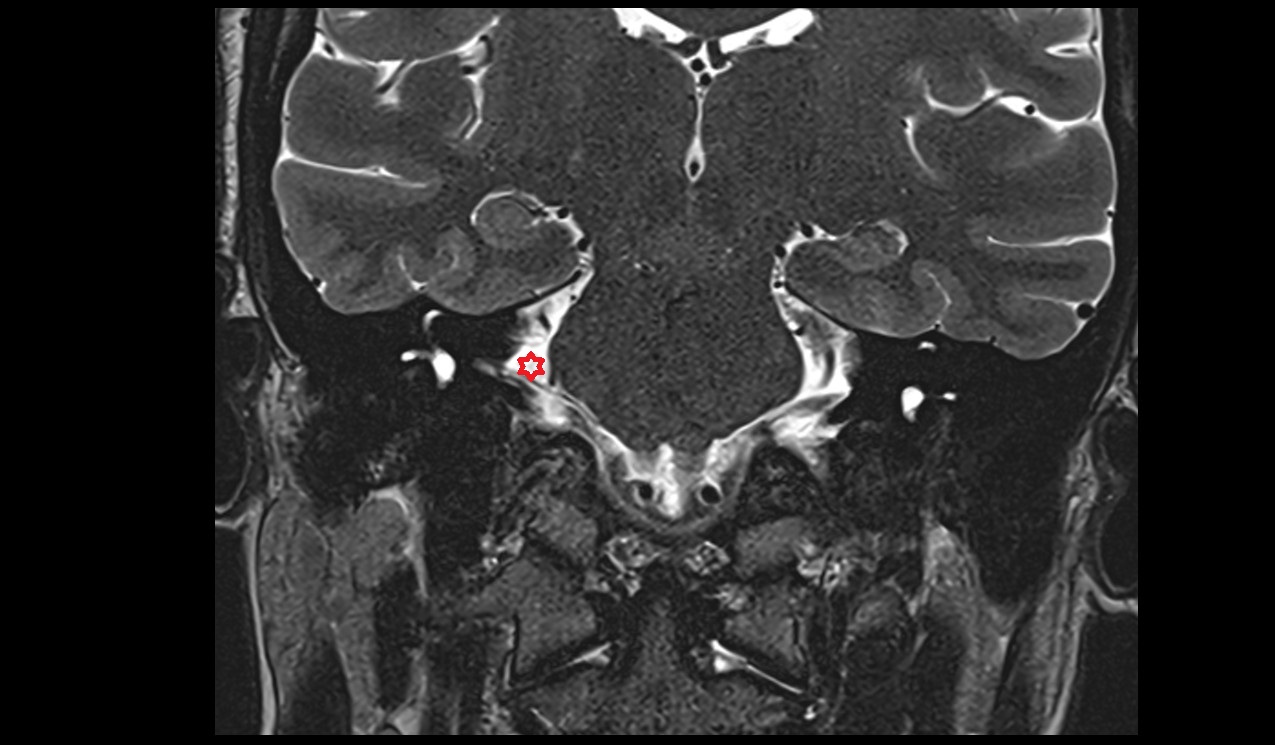

- Lateral aperture of fourth ventricle (foramen of Luschka)